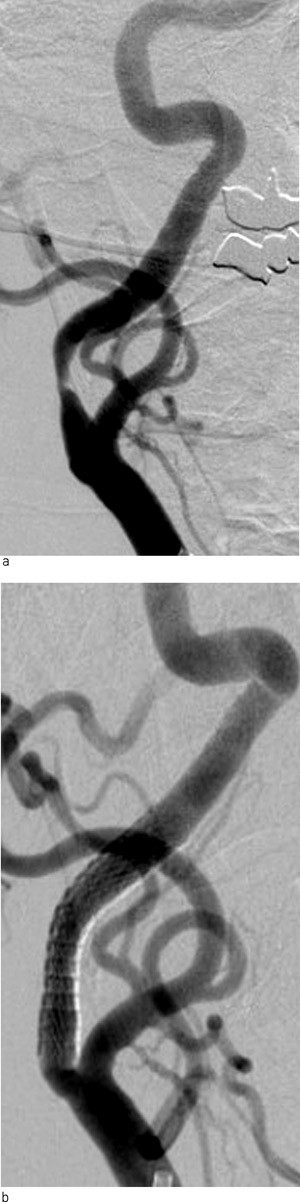

Behandling utføres av nevroradiologer. Pasienten er våken, men sederes etter behov. Acetylsalisylsyre og klopidogrel startes minimum fire dager før prosedyren og kontinueres i ett år etter inngrepet. Det gis heparin under prosedyren. Blodtrykket monitoreres og styres som ved kirurgi. Det er beredskap for behandling av arytmier som kan forekomme ved ballongdilatasjon i carotisbifurkaturen. Tilgang er vanligvis fra høyre arteria femoralis, og det benyttes spesielle føringskatetre og selvekspanderende stenter (fig 2). Før stenten føres opp og dilateres, plasseres en beskyttende filterståltråd distalt i a. carotis for å samle opp mikropartikler som løsner under prosedyren. Deretter snøres filteret sammen og fjernes via føringskateteret. Et lite antall pasienter ble behandlet kun med ballongdilatasjon uten stent.